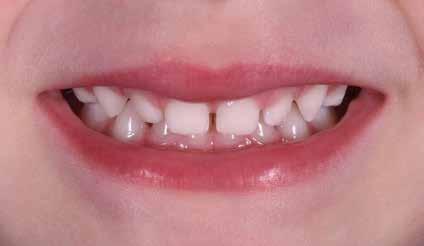

Il check-up ortodontico del paziente da due a sei anni Per i piccoli pazienti di questa fascia di età la diagnosi si baserà sulla documentazione fotografca, sulla documentazione video e sull’anamnesi familiare per capire se sono presenti malocclusioni in famiglia; in questa fase è molto importante analizzare tutti e due i genitori del piccolo paziente, per evitare di trovare sorprese nel corso della terapia (Baccetti et al. 2011).

Non è sempre possibile sottoporre il paziente a queste indagini diagnostiche; per migliorare il successo e la riuscita del protocollo è necessario un approccio meticoloso ed una serie di informazioni e un’analisi dettagliata dei comportamenti per rendere il paziente collaborante, come descritto precedentemente. Questo tipo di documentazione non prevede radiografe vista la giovane età del paziente e, quindi, la diagnosi dovrà basarsi sull’esame clinico, fotografco e sull’anamnesi familiare (Snow 2005) Figg. 22-46